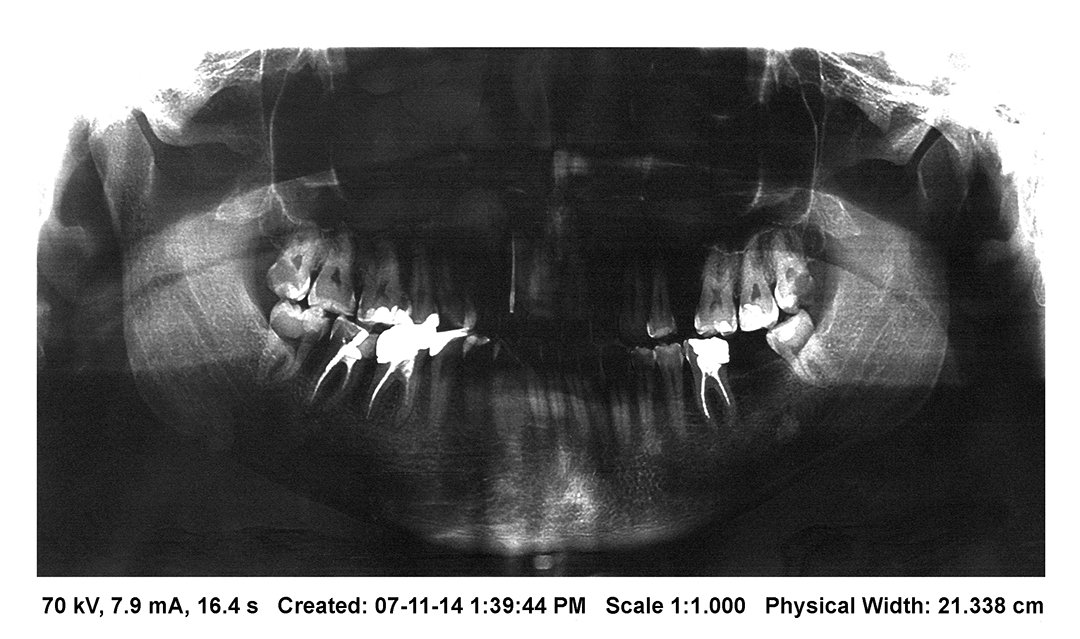

K & T(eeth)